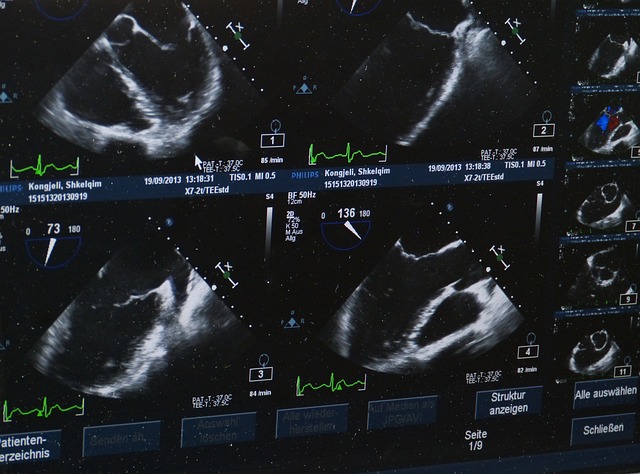

L’échographie rénale et vésicale est généralement le premier examen prescrit face à une

hématurie. Elle est non invasive, sans irradiation, et offre une bonne visualisation des reins

et de la vessie. Elle permet de détecter des calculs, des masses rénales ou une rétention

urinaire. Toutefois, elle présente des limites, notamment pour évaluer les voies excrétrices

supérieures ou pour identifier des lésions urothéliales de petite taille.